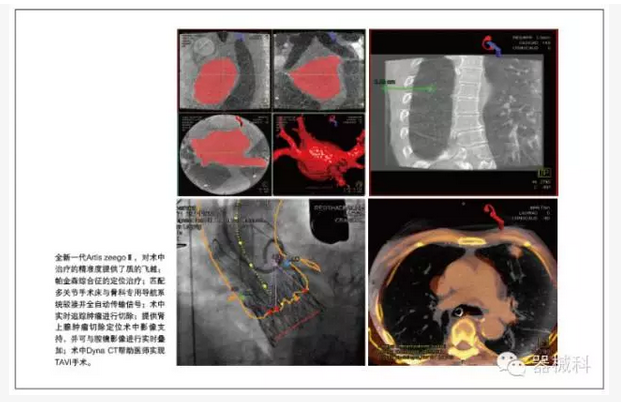

在胸外科肺部腫瘤及肝臟腫瘤微創(chuàng)手術的治療最前沿,西門子復合手術室提供術中腫瘤定位等實用技術支持,通過實時的Dyna CT和術前MR圖像融合,包括超聲及術中腔鏡影像,來確定腫瘤的位置,并術中實時追蹤腫瘤進行切除。

在骨科領域,Artis zeego與傳統(tǒng)小C臂相比,劑量低,影像更清晰,并可提供特殊體位的3維重建和清晰的CT影像,巨大的投照面積,可提供全髖,肩關節(jié),全胸椎,全腰椎的一次成像,機器人提供的靈活投照角度,且具備投照記憶功能,大幅減少了術中劑量,縮短了手術時間;而且機器人可匹配多關節(jié)手術床與骨科專用導航系統(tǒng)駁接并全自動傳輸信號。

特別是術中實時的CT評估,對于術中治療的精準度提供了質(zhì)的飛越。其實,對于全新一代Artis zeegoⅢ,他的神奇還包括6秒360度極速旋轉采集,十字繡激光定位引導穿刺,多臟器的iFlow血流編碼及PBV功能成像。以及我們和內(nèi)鏡微創(chuàng)界的達芬奇機器人強強聯(lián)合,開展更尖端復雜的精準微創(chuàng)手術。